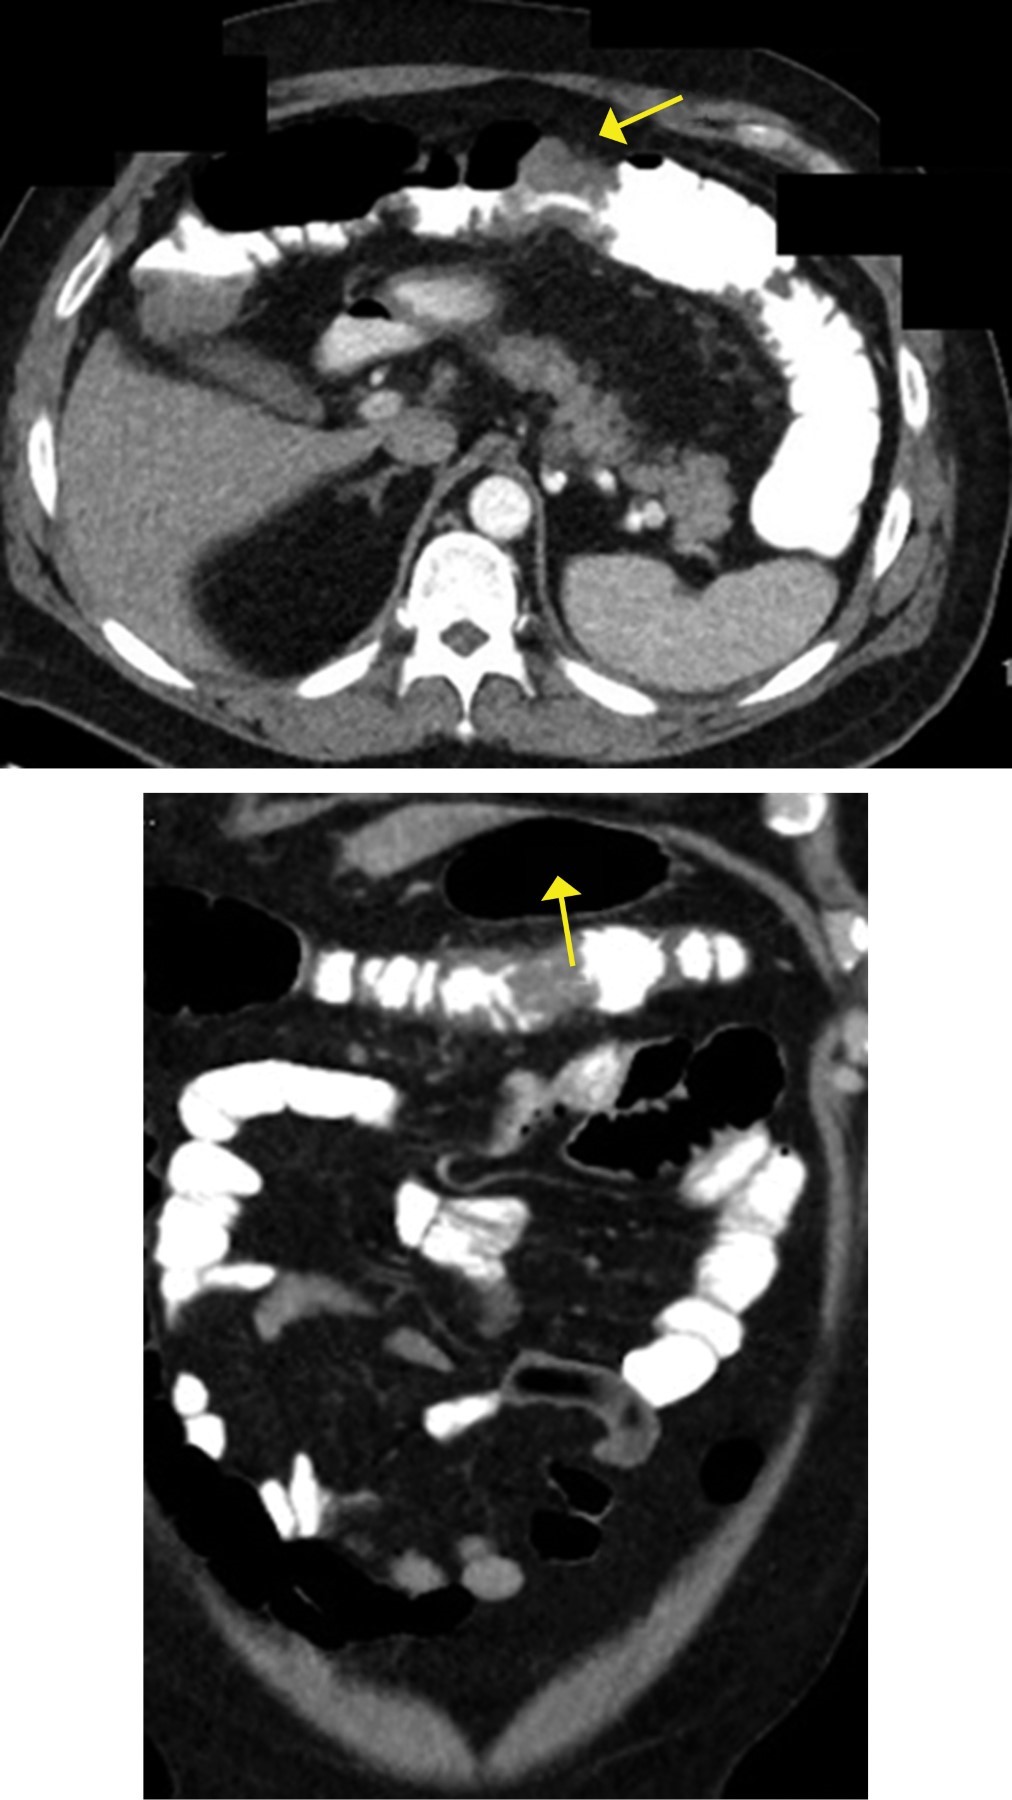

The study was complemented with an endoscopy of the upper gastrointestinal tract showing a diffuse micronodular surface in the upper portion of the body of the stomach, without duodenal polyps (Figure 2), and a thoracoabdominal computerized tomography (CT) scab with IV contrast revealed a transverse colon tumor with peri-colonic fat infiltration conditioning partial obstruction, as well as the presence of para-aortic lymphadenopathies (Figure 3). Laboratory studies showed hemoglobin: 9.0 g/dl, total protein: 5.8 g/dl, albumin: 3.0 g/dl and carcinoembryonic antigen: 131 ng/ml.

Figure 1

Figure 3